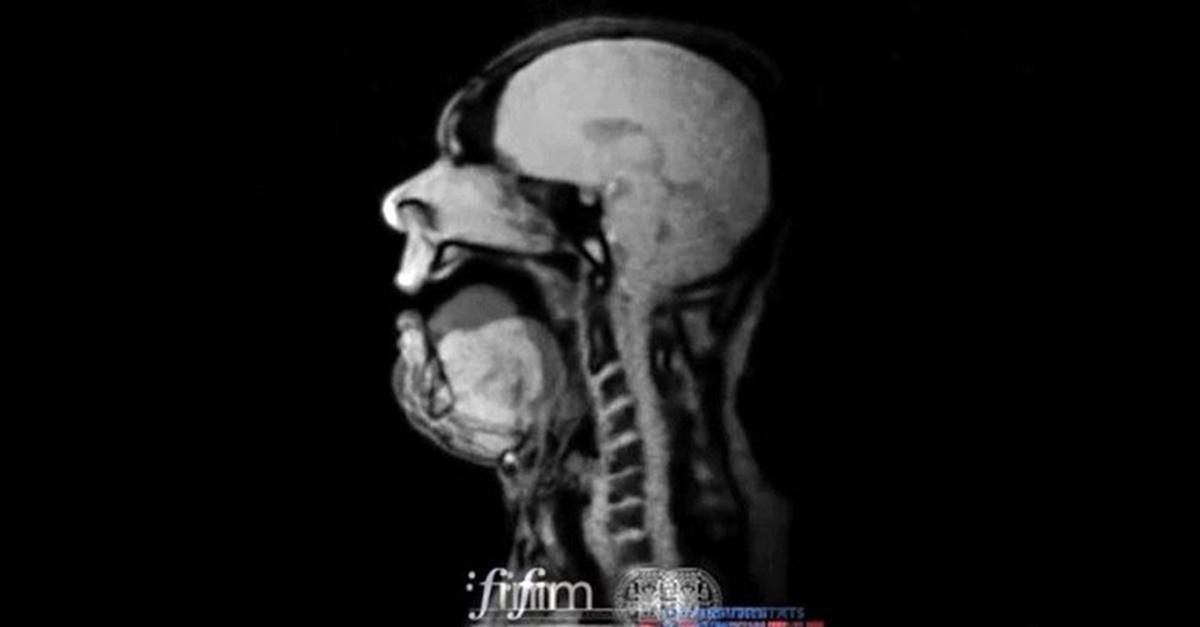

An MRI Of opera singer Michael Voll performing Wagner

MRI image of an opera singer, singing.

German baritone Michael Volle performed "Song to the Evening Star" by German composer Richard Wagner while inside of an MRI scan to give people a never-before-seen look at how an opera singer produces such a haunting sound. It's a pretty freaky-looking image, but shows the amazing control these performers must have to hit such powerful notes.